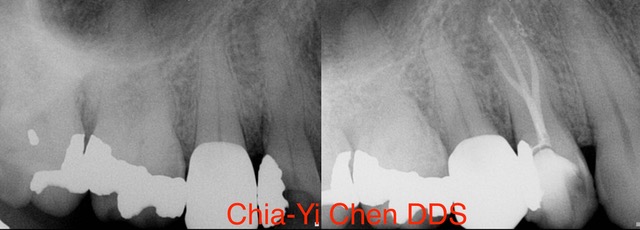

The Procedure of a Root Canal Treatment

To begin, our endodontist will start by numbing the area around the affected tooth using local anesthesia. This ensures that you feel little to no pain during the procedure. Once you are numb and comfortable, our endodontist will create a small access hole in the crown of your tooth. Through this access point, they will carefully remove any infected or damaged pulp from within the roots and chambers of your tooth. This helps eliminate any infection and prevents further damage to surrounding tissues.

After cleaning out all traces of infection, our endodontist will then shape and sterilize the canals before filling them with a rubber-like material called gutta-percha. This material provides stability and prevents reinfection.